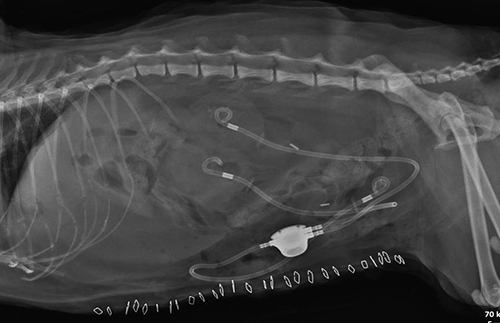

- 외과센터 소개 - 외과수술 종류 - 주요수술 안내